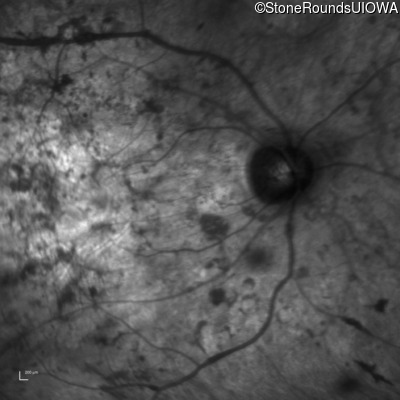

Infrared Fundus Photograph - Right - Hand Motion

Exemplar